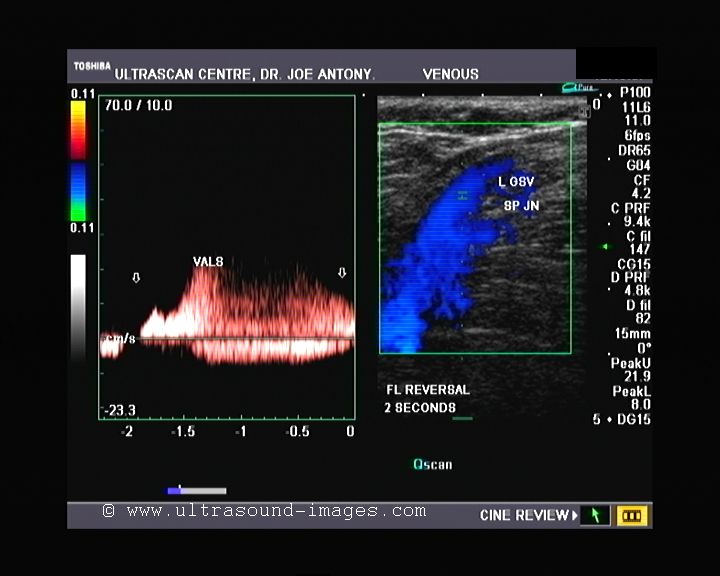

The answer to that quiz is: it is a case of incompetence of the saphenofemoral junction with incompetence of multiple valves of the great saphenous vein resulting in varices in the left leg. These varicose veins are associated with incompetent and distended perforator veins in that area. This is well demonstrated in the color Doppler images and videos posted on that blog.